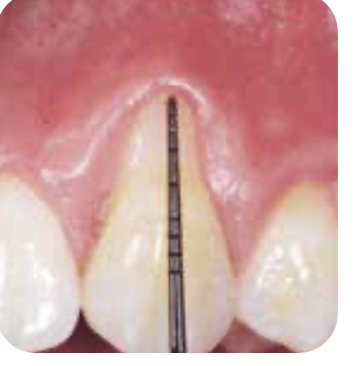

🌿 잇몸 상태 비교

BEFORE

AFTER염증 감소와 잇몸 건강 회복을 확인할 수 있습니다